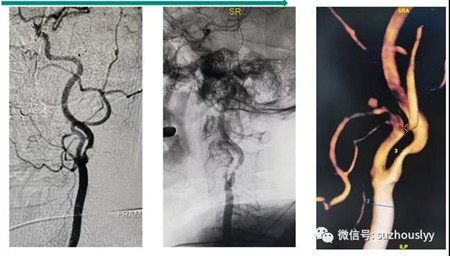

患者余某某,女,73岁,因“发作性头晕1年余,加重2天”入院。患者来到我院神经外科,经过脑血管造影等检查后发病原因得以明确:头颅DSA造影提示:左侧颈内动脉起始部狭窄(重度),侧枝循环代偿欠佳。

2021年05月08日,由我院神经外科脑血管病组郭志强、岳培东、张潜、钱金明、张磊等医师手术团队为该患者进行了左侧颈动脉内膜剥脱术。术后复查DSA见狭窄解除,血管通畅,脑血流增加,患者头晕等症状改善,精神更加饱满。